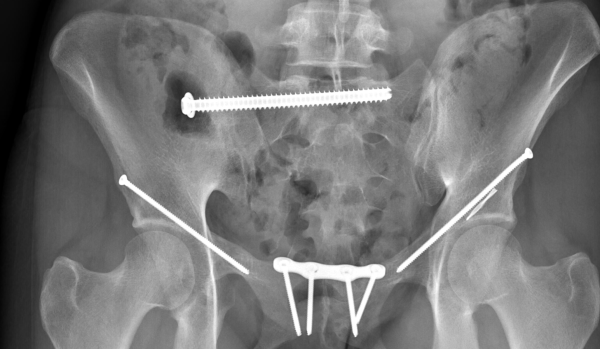

The impact of flat landing left Grace severely concussed and internally bleeding. When they airlifted her to the Royal North Shore Hospital, a full body CT scan revealed six unstable fractures in her pelvis. After a night in ICU, she had an emergency surgery the following morning to stabilise the pelvis and broken sacrum with three screws.

After two weeks of this, one of Grace’s fractures had moved, and she needed a second surgery, leaving her with another four screws and a plate.

“I was airlifted from the accident to Royal North Shore hospital. That night, I was put in ICU, and the next morning, I had my first surgery. Two weeks later I had to have a second unexpected surgery. I stayed in the hospital for a total of 31 nights. Those two surgeries left me with seven screws and a plate. I came home, still non-weight bearing for four weeks. There’s a staircase at the front of our house, so I was lifted in by the paramedics and then confined to my room and the kitchen, it started to feel a little claustrophobic by the end…